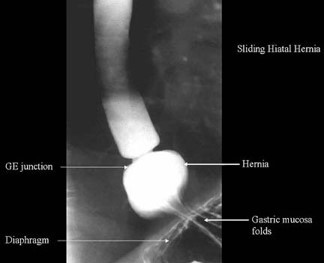

What is a hiatus hernia?

Herniation of part of the stomach through diaphragmatic oesophageal hiatus

Predisposes to/worsens reflux- wide hiatus

Types?

Sliding

Paraoesophageal

Investigations?

Barium swallow